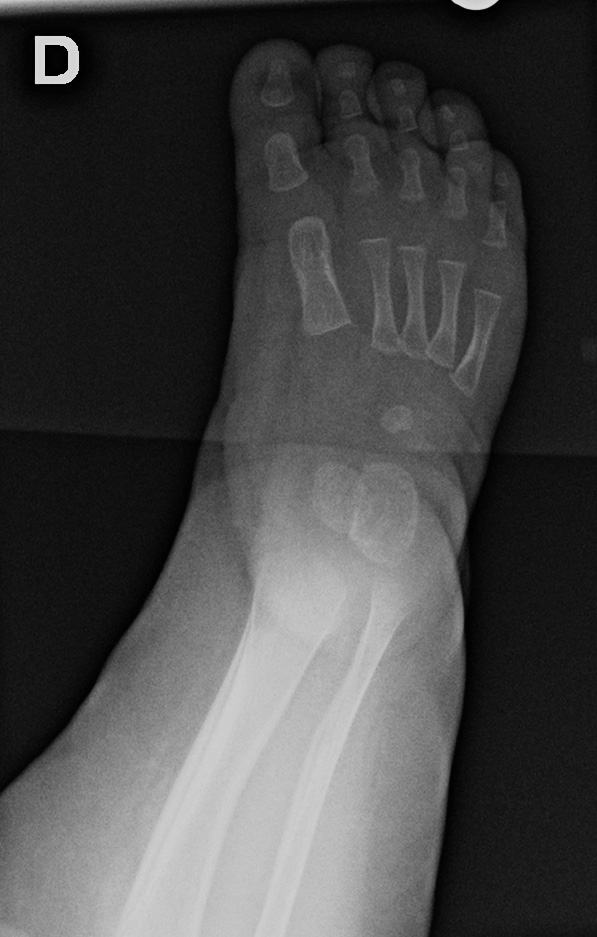

0-hour-old male:

Feet deformity.

On the right side, the anteroposterior talo-calcaneal angle (Kite's angle) is decreased to 7° (normal between 20 and 40°). On the lateral view of Turco, the talo-calcaneal angle is 30° (normal over 35°). In short, on the anteroposterior view, the talus and calcaneus are more parallel than expected (normaly they are diverging).

On the right anteroposterior view, the talus-1st metatarsal angle is measured at -7° (normal between 0 and 20°). The 1st metatarsal is medial to the talus because of the forefoot deviation in varus and adductus.

On the left side, the talus is not ossified enough to take measurements. Global alignment, however, suggests a left club foot of similar severity than the right.